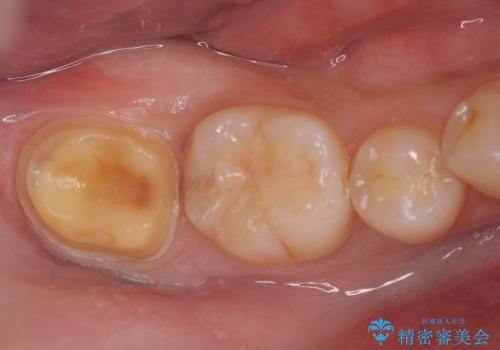

- 右下奥歯の詰め物が繰り返し欠けるとの主訴で来院されました。レントゲンとお口の中を詳細に診査した結果、以前の詰め物が咬み合わせの強い力に耐えきれず、また歯との適合も不十分であることが確認されました。患者様と相談し、今回は強度と耐久性に優れ、見た目も自然なセラミッククラウンで修復する治療計画を立案しました。これにより、再治療のリスクを減らし、長期的に安定した咬み合わせの回復を目指します。

治療では、まず古い詰め物を丁寧に取り除き、虫歯がないか確認しながら歯を丁寧に形を整えました。その後、精密な型取りを行い、患者様の歯の色や形に合わせたオーダーメイドのセラミッククラウンを作製しました。セラミックは天然歯のような透明感があり、非常に審美性に優れています。また、金属を使用しないため、金属アレルギーの心配もありません。